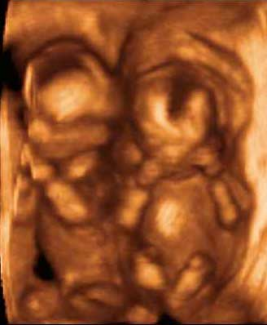

Feto de 29 Semanas Feto Completo Gemelos Manos Pies

Gemelos